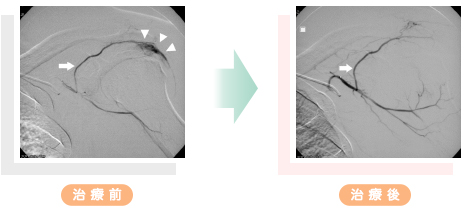

手技的解説 運動器カテーテル治療 臨床画像 35巻14号 医書 Jp